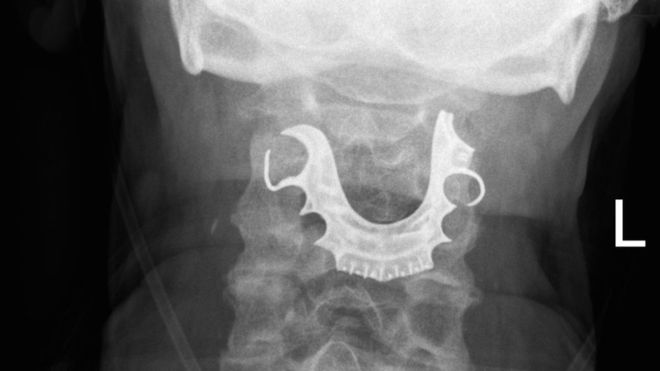

Los médicos encontraron la dentadura postiza del hombre en su laringe más de una semana después de operarlo.

Los médicos encontraron la dentadura postiza del hombre en su laringe.

Cuando el hombre regresó nuevamente dos días después, los médicos revisaron su garganta y fue entonces que encontraron un objeto semicircular sobre sus cuerdas vocales.

Y todo empezó a cobrar sentido cuando el hombre les contó que había perdido su dentadura postiza durante su operación.

Una vez que que le hallaron el objeto en la laringe, ocho días después de la primera operación, el paciente tuvo que ser intervenido nuevamente para remover la dentadura postiza de su cuerpo.